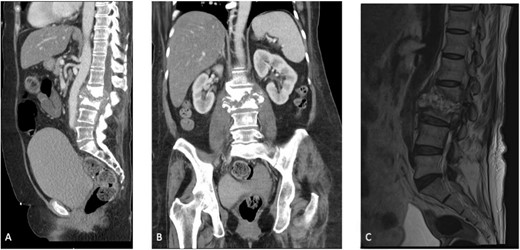

The patient was placed in the operating room for anterior lumbar interbody fusion via thoracoabdominal (TA) incision for retroperitoneal exposure. The patient was placed in the right-lateral decubitus position. The 10th rib interspace was identified, and a curvilinear incision was made from the midaxillary line and extended anteriorly and inferiorly toward the umbilicus. The retroperitoneal plane was entered, and the 11th rib was cut and morcellated for lumbar cage placement. The diaphragm was divided radially with electrocautery to further expose the abdominal cavity and retroperitoneal space. The lateral border of the psoas muscle was exposed and dissected into the anterior vertebrae L1–L4. The aorta and abdominal viscera were retracted toward the patient’s right side using an Omni retractor. Copious necrotic tissue and caseating granulomas were removed. The L2–L3 vertebrae were exposed, corpectomy was performed, and a titanium cage was placed with a plate spanning from L1 to L4 (Fig. 2A and B). To achieve added stability, a second surgery for posterior percutaneous screw placement without lumbar fusion was performed (Fig. 3). The patient recovered without complications and was subsequently discharged to a skilled nursing facility, and ultimately home. At the 1-month follow-up visit, the patient’s TA incision had completely healed, and there was no evidence of recurrent infection.

(A) Anterior intraoperative fluoroscopy demonstrating final titanium cage placement spanning from L1 to L4. (B) Lateral intraoperative fluoroscopy demonstrating final titanium cage placement spanning from L1 to L4.